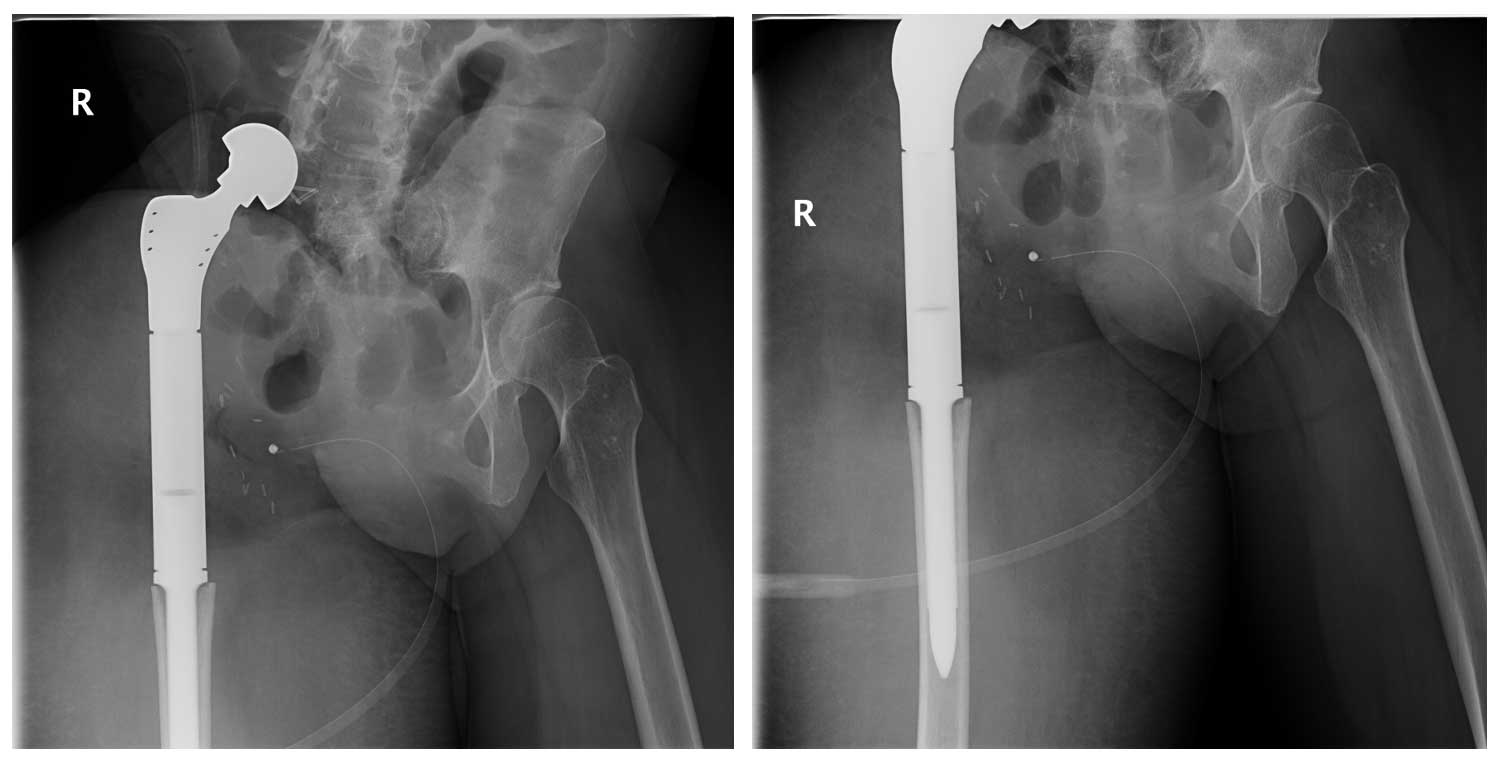

Ameliyat Sonrası: Röntgende internal hemipelvektomi sonrası proksimal femur tümör protezi ile kalça transpozisyonu uygulanımı görülmekte.